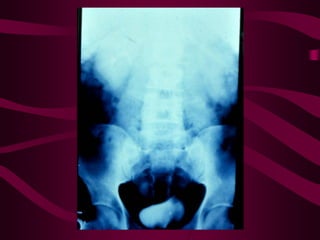

Este documento describe la tuberculosis genitourinaria. Afecta más a hombres que a mujeres. Se transmite principalmente a través de la infección pulmonar primaria y luego se disemina a través de la sangre a los riñones u otros órganos. Causa lesiones como granulomas y necrosis si no se controla, lo que puede provocar complicaciones como abscesos e insuficiencia renal. Se diagnostica mediante pruebas de orina y tratamiento con medicamentos durante varios meses.